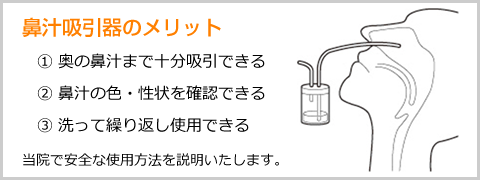

● 鼻汁吸引などご家庭でできる治療方法も紹介し指導いたします。

鼻汁吸引器(小児向け)/ATOM羊水吸引カテーテル

アトムメディカル

市販品の鼻汁吸引では鼻が吸えないというお声をもとに、当院で使用している鼻汁吸引器です。吸引された鼻水が容器の中にたまるため、鼻汁の色や性状(粘り度)を目で確認することができます。また得られた鼻水から直接細菌培養検査が行えるので、検査が必要なとき再度鼻に綿棒を入れて痛い思いをすることがありません。自宅でも鼻汁吸引ができるよう、吸引の仕方を当院で説明・指導いたします。